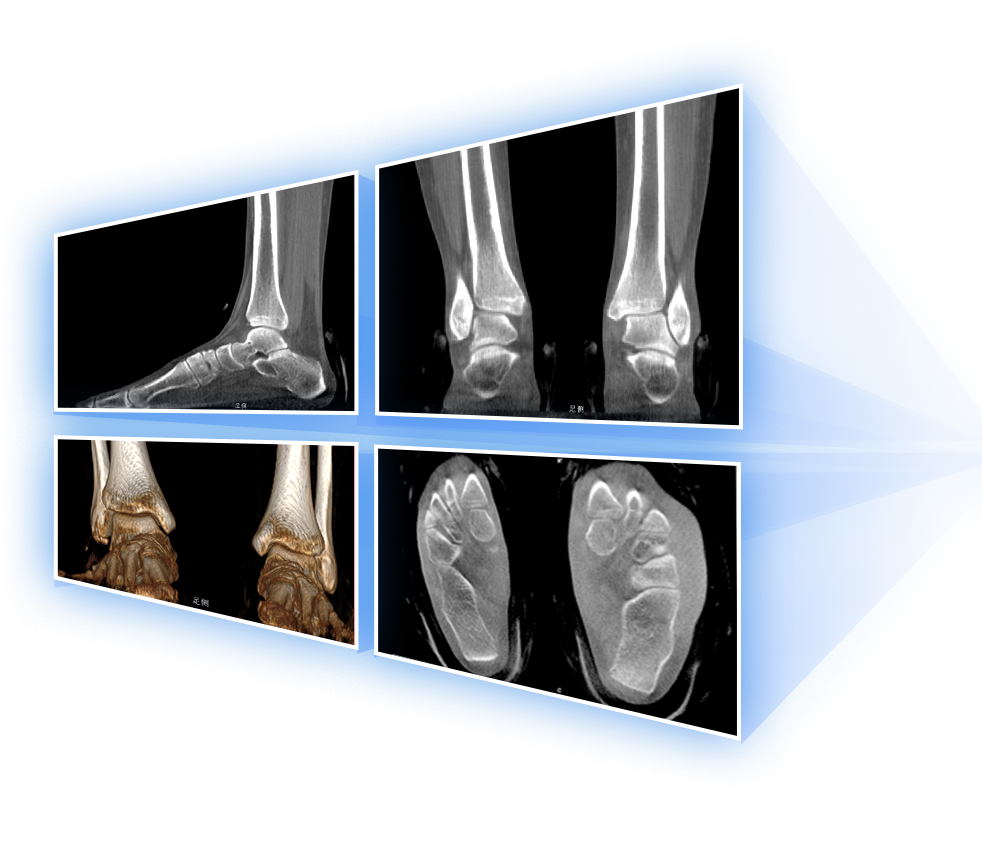

足踝

精准诊断

手术方案规划

术后随访